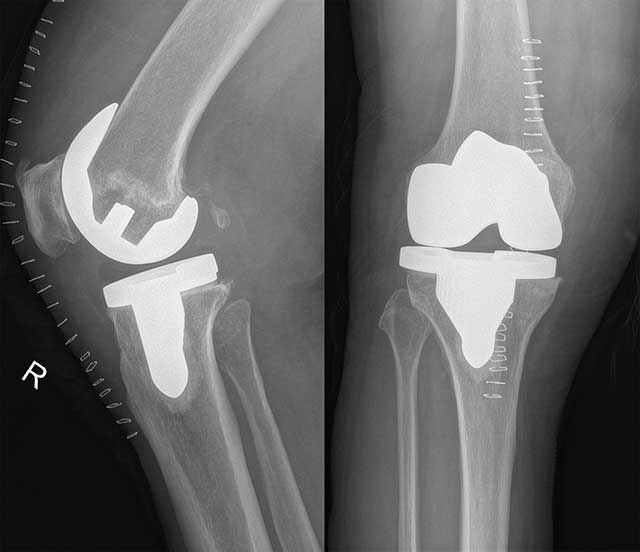

人工膝關(guān)節(jié)置換術(shù)示意圖 這情況若不處理,只會加重甚至不能走,可這樣解決…… 對于余婆婆這種情況,新會區(qū)中醫(yī)院骨二科膝關(guān)節(jié)??朴修k法處理。該科葉英文主任是我區(qū)第五批中青年優(yōu)秀專家和拔尖人才,對治療膝關(guān)節(jié)疾病有豐富的經(jīng)驗。葉主任在詳細(xì)了解余婆婆的情況后,就果斷提出了“人工膝關(guān)節(jié)置換術(shù)”的方案。余婆婆和家人一聽要手術(shù),難免心里直打鼓“還能扶拐走幾步呢,一下子就要動手術(shù),會不會動靜太大了呢?”,見到家屬的顧慮,葉主任用專業(yè)與通俗相結(jié)合的方式作出了解釋:余婆婆膝關(guān)節(jié)的骨和軟骨在長年累月的活動中已經(jīng)磨損變形,傳統(tǒng)的保守治療所起的效果將越來越有限?!叭斯はリP(guān)節(jié)置換術(shù)”是指用人工生物材料置換膝關(guān)節(jié)中已破壞的骨和軟骨,簡單地說,就是將已磨損、破壞的關(guān)節(jié)面切除,植入人工關(guān)節(jié)代替損壞的關(guān)節(jié),從而讓膝關(guān)節(jié)功能恢復(fù)……家屬聽解釋后,顧慮消除了。 5月23日,葉英文主任帶領(lǐng)主管醫(yī)生童新延等骨二科團隊給余婆婆施展了“人工膝關(guān)節(jié)置換術(shù)”。雖然是“傷筋動骨”的手術(shù),但手術(shù)過程及術(shù)后余婆婆都沒有出現(xiàn)太多的疼痛感,實現(xiàn)了手術(shù)及術(shù)后過程無痛、無血、無栓化管理。第二天,余婆婆已經(jīng)可以在醫(yī)護的指導(dǎo)下下地行走了!

徐婆婆術(shù)前及術(shù)后X光圖像對比 膝關(guān)節(jié)好腿就能活動行走,健康和生活質(zhì)量就重拾回來…… 目前,“人工關(guān)節(jié)置換術(shù)”已經(jīng)被認(rèn)為是重度骨性關(guān)節(jié)炎最有效、最成功的手術(shù),在我國各大城市已廣泛開展。人工膝關(guān)節(jié)置換術(shù)能消除膝關(guān)節(jié)疼痛,糾正膝關(guān)節(jié)畸形,大大改善膝關(guān)節(jié)功能,提高生活質(zhì)量。新會區(qū)中醫(yī)院骨傷科開展膝關(guān)節(jié)置換術(shù)已有20多年歷史,近年來,醫(yī)院膝關(guān)節(jié)專科緊跟醫(yī)學(xué)科技發(fā)展潮流,不斷派出高年資醫(yī)生到上級醫(yī)院進修學(xué)習(xí)先進經(jīng)驗,醫(yī)療團隊的技術(shù)力量不斷增強?,F(xiàn)在,葉主任帶領(lǐng)團隊通過微創(chuàng)手段,運用人工關(guān)節(jié)替換嚴(yán)重退變而毀損的關(guān)節(jié),并采用目前最先進的手術(shù)方法整形后,能更好地解決患者的病困,余婆婆就是其中一例。運用這種方法可將中老年人常見的重癥膝關(guān)節(jié)骨性關(guān)節(jié)炎得到解決,讓健康和生活質(zhì)量重拾回來。